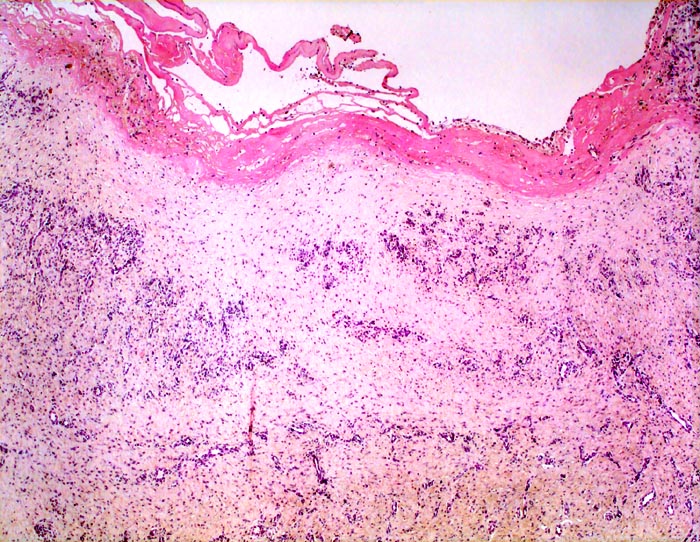

chronische Bursitis

Entzündung / Reparatur

Bursa praepatellaris

Bursawand fibrös (= narbig) verdickt. Der Bursainnenseite aufgelagerter Fibrinpelz. Bursawand mit Organisationsgewebe mit vielen bäumchenartig gewucherten kapillären Gefässen, dazwischen zellarmes Narbengewebe.

Der anatomische Aufbau der Bursa entspricht dem einer Gelenkkapsel oder Sehnenscheide; von innen nach aussen:

- Ein- bis zweischichtige Zellschicht aus Synoviozyten

- Lockeres, zell- und gefässreiches Stratum synoviale

- Straffes Stratum fibrosum

Histologie

25